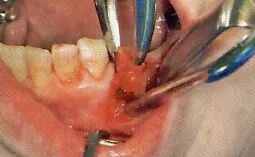

3切开

利用手术刀·电刀等器械将手术区域的牙龈切开

医生利用手术刀进行切开。首先避免吸唾器在手术刀的切开路线上阻碍医生的操作。切开线设计分为三角形,四边形和沿牙龈缘等各种不同的形状。口腔卫生士一定要事先与医生确认切开设计的形状。

切开线设计(有残根的情况)

务必保证切开线区域的视的野晰度(切开前要吸引唾液,切开过程中要吸引血液)

切开前,一定要将切开线区域的唾液吸引干净。如果切开区域有唾液残留的话,会造成医生无法找到切开线路。切开时,从切开线区域会有血液溢出。将吸唾器放置到出血点,正确找到出血点才能更加有效的将溢出的血液吸引干净。